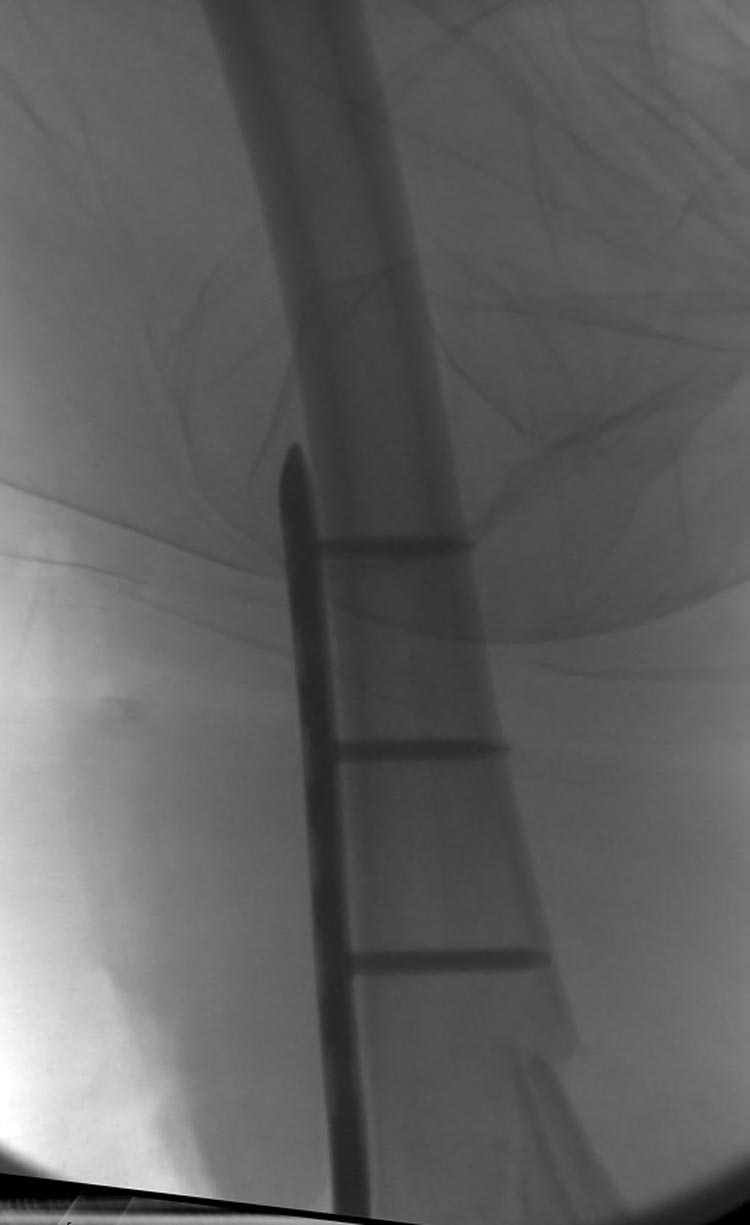

Смело открывайте сустав, собирайте мыщелки на один спонгиозник или болт стяжку и под него вводите штифт из стандарного места введения. В данном случае хорошо подойдет универсальный бедренный штифт СнМ.